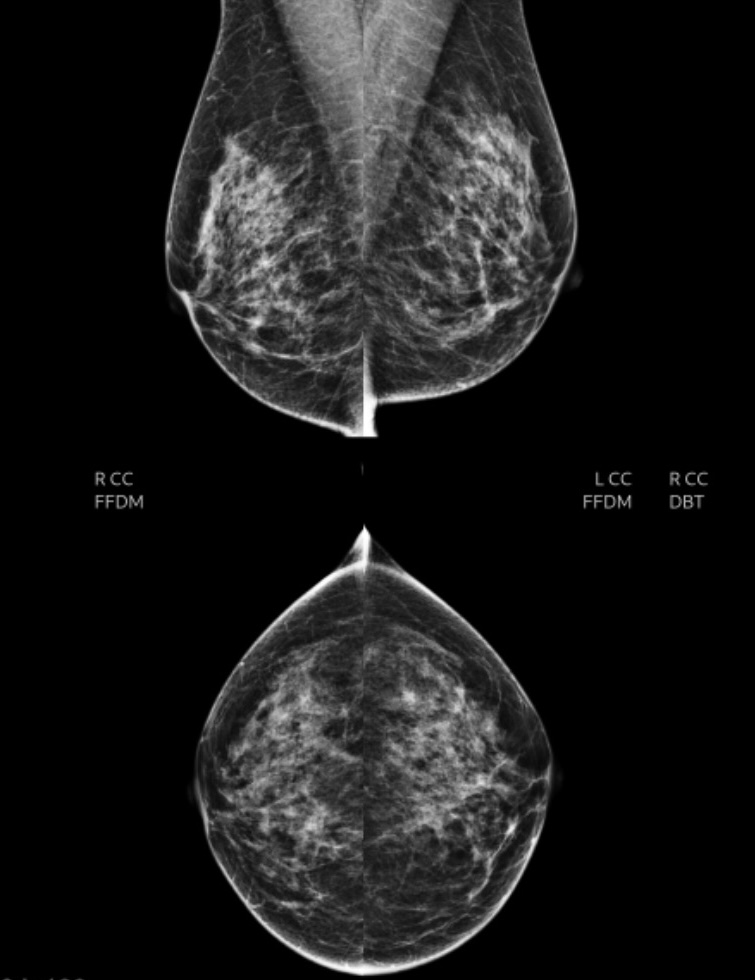

Anyway, we are at the breast center together because I got recalled after my recent regular annual mammogram. Apparently, there were some dubious-looking spots on that reading, so here I am, back for another uncomfortable breast-squishing, only this one is to be followed by an ultrasound.

Thankfully, I got my results immediately today. Turns out I have some pea-sized cysts on one breast. I almost cried with relief. Nothing to be concerned about — it transpires that cysts are extremely common, and they do not become cancerous. Also, if they get too big, they can be extracted.